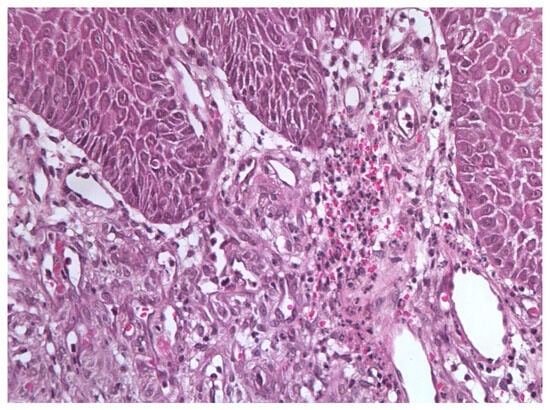

Figure 5.

Excisional biopsy specimen (November 2015) showing endothelial cell clusters with mild atypia, numerous vascular spaces, and scattered microthrombi with hemosiderin deposits.